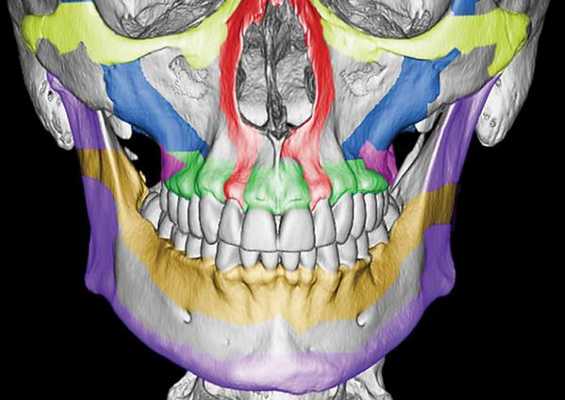

Чаще всего переломы классифицируют по Рене Ле Фору. Этот французский хирург систематизировал и описал формирующиеся повреждения костей средней зоны лица экспериментально: на головы свежих человеческих трупов он оказывал разные по направлению и силе воздействия по типу тупой травмы. Именно так и было обнаружено, что большинство линий переломов проходит по трём типам [1] :

- | тип — нижний, или горизонтальный тип, перелом Герена — Ле Фора. Перелом проходит над альвеолярным отростком и нёбным отростком через боковую и переднюю поверхности верхней челюсти, от крыловидных отростков основной кости к краю грушевидного отверстия.

- || тип — средний, или пирамидальный перелом, суборбитальный перелом. Линия перелома проходит через корень носа, внутреннюю стенку глазницы и далее — через нижнеглазничную щель кпереди по нижней стенке глазницы к месту альвеолярно-скулового контрфорса с переломом крыловидных отростков. Проще говоря, верхняя челюсть единым блоком "отсоединяется" от остальных костей средней зоны лица.

- ||| тип — верхний тип (поперечный, суббазальный, он же черепно-лицевое разъединение). Самый грозный вид перелома верхней челюсти, когда происходит отрыв верхней челюсти вместе со скуловыми костями от мозгового черепа. Как правило сочетается с тяжёлыми повреждениями головного мозга [3] .

Отличительные признаки каждого типа проявляются по уровню подвижности фрагментов, тяжести состояния больного и данным дополнительных методов исследования (компьютерной томографии).